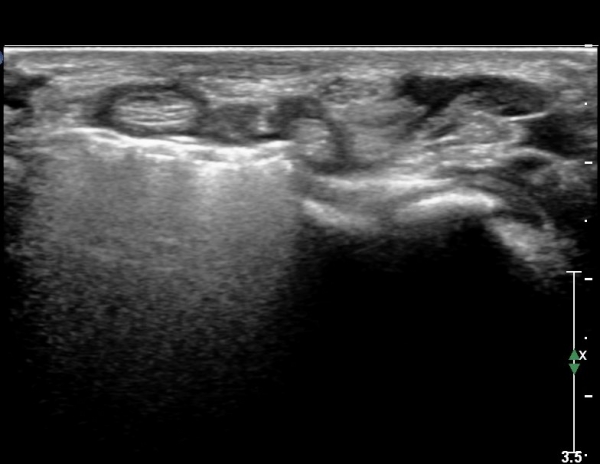

º¸ÀÌÁö ¾ÊÀ¸³ª  FPL ÈûÁÙÀÇ Àú¿¡ÄÚ ºÎÁ¾ÀÌ °üÂûµÇ°í(»çÁø 2, 3) ³»°íÁ¤¹°ÀÌ FPL °ú Á¢ÃËÇϰí ÀÖÀ½ÀÌ °üÂûµÊ(»çÁø 3)

ŽÃËÀÚ¸¦ Á¶±Ý ¸»´ÜÀ¸·Î À̵¿ÇÏ´Ï FPL Å©±â°¡ ±Þ°ÝÈ÷ °¨¼ÒÇÔ. FCR,  FDP ÁÖº¯ ¹Ì¼¼ÇÑ ¼ö¾×Àú·ù °üÂûµÊ(»çÁø4, 5)

ŽÃËÀÚ¸¦ Á¶±Ý ´õ ¸»´ÜÀ¸·Î À̵¿ÇÏ´Ï FCR¿Í FDP »çÀÌ¿¡¼­ Àú¿¡ÄÚ »óÅÂÀÇ FPL °¡ °üÂûµÇ°í °íÁ¤¹°¿¡ ÀÇÇÑ

¾Ð¹ÚÀÌ °üÂûµÊ(»çÁø 6, 7)